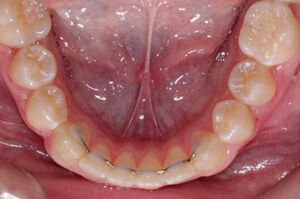

Fixed retainers consist of wires bonded behind the bottom and/or top teeth. Because it is often kept in place for life, patients must be sure to take care of it and keep it clean.